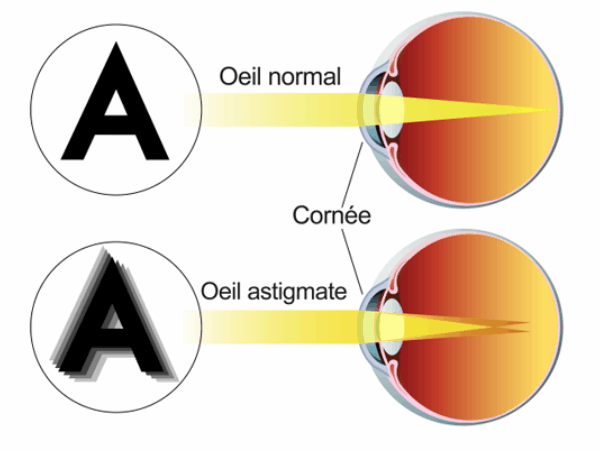

Les principaux défauts de la vision:

- Chez quelqu'un d'astigmate, la vision est floue, de près comme de loin.La cornée est déformée ; au lieu d’être sphérique, elle est plus bombée dans un sens (par exemple verticalement) que dans l’autre (par exemple horizontalement). L’image se forme sur deux plans différents.